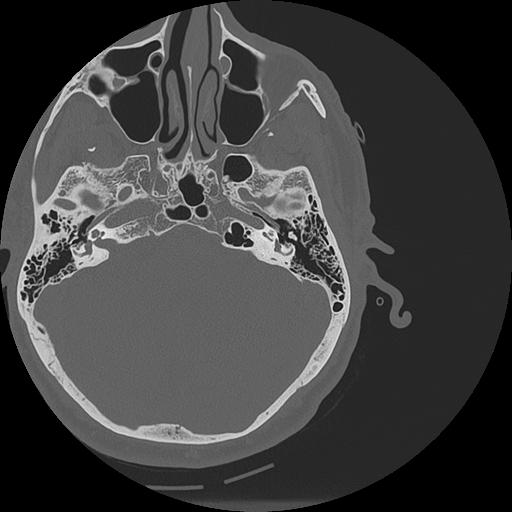

7 HUESO,,Vol,0.5,HUESO,,